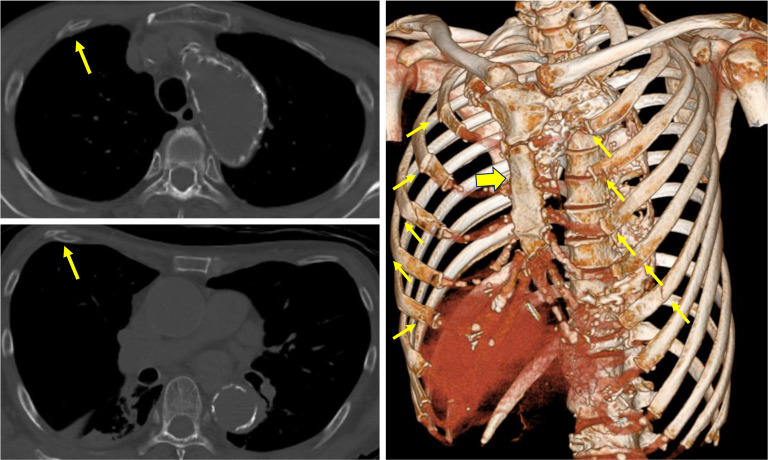

Case description: A 72-year-old woman presented to the emergency department with ventricular fibrillation caused by acute myocardial infarction. The patient underwent cardiac catheterization and coronary artery stenting following cardiopulmonary resuscitation (CPR). The patient was referred to Fukaya Red Cross Hospital owing to dyspnea caused by a flail chest following CPR. Being an elderly woman, the supporting tissues of the thorax had weakened, and she had a pronounced flail chest, a labored breathing pattern, and severe respiratory distress. Although there is the disadvantage that cardiac massage would become difficult, the cardiologist determined that cardiac function had stabilized after stent placement and that the likelihood of cardiac massage being necessary was extremely low, and therefore it was determined that repair using the Nuss method would be preferable. Two Nuss bars were inserted. Following the procedure, her respiratory condition improved, and she was discharged. Eight months later, the collapse of the anterior chest wall had resolved, and the Nuss bars were removed. However, the patient developed bilateral pneumothoraces post-removal. Thoracic drainage was performed, leading to improvement, and she was subsequently discharged.